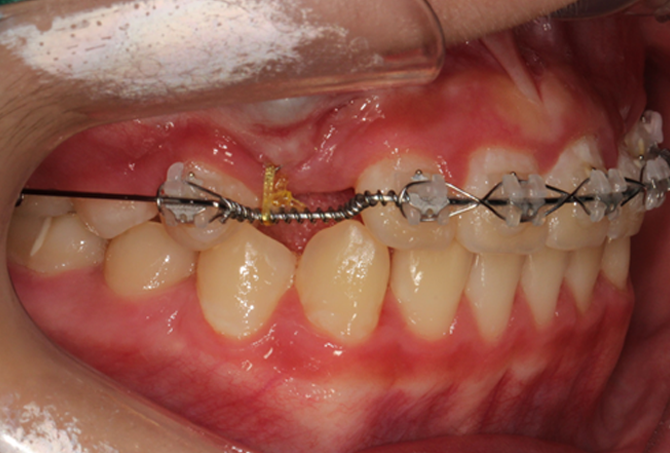

OPTHODONTIC OPTIONS

설측교정과 콤비교정,

무엇이 다른가요?

보이지 않는 교정을 원하시는 분들에게

설측교정과 콤비교정은 대표적인 선택지입니다.

설측교정은 교정장치를 상악과 하악 모두 안쪽에 부착하는 반면,

콤비 교정은 상악은 안쪽,

하악은 바깥쪽에 부착

한다는 차이점이 있습니다.

• STEP 02 설측 맞춤형 브라켓 지그 제작

교정전문의와 CAD/CAM전문가의 디자인으로

개별적인 설측 지그를 제작합니다.

• STEP 03 장치 부착 및 치료

IDBS(간접부착)방식을 이용하여

정밀한 위치에 장치를 부착합니다.